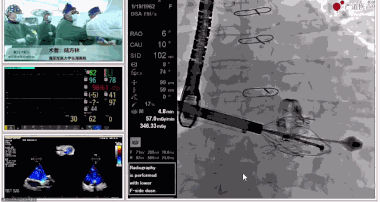

圖片

▲瓣膜植入過程